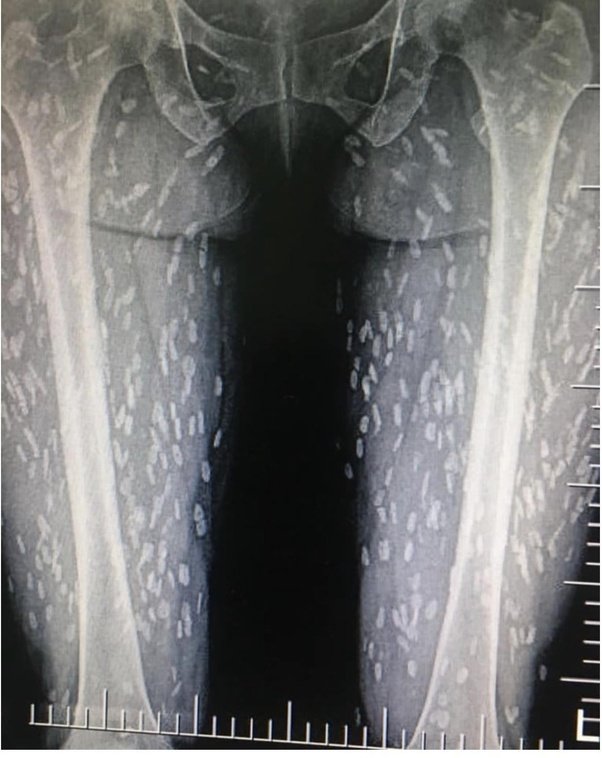

However, people still get infected in parts of the world where the pigs are not in a controlled environment. The white spots in the X-ray picture below are cysts of the parasite in an infected human.